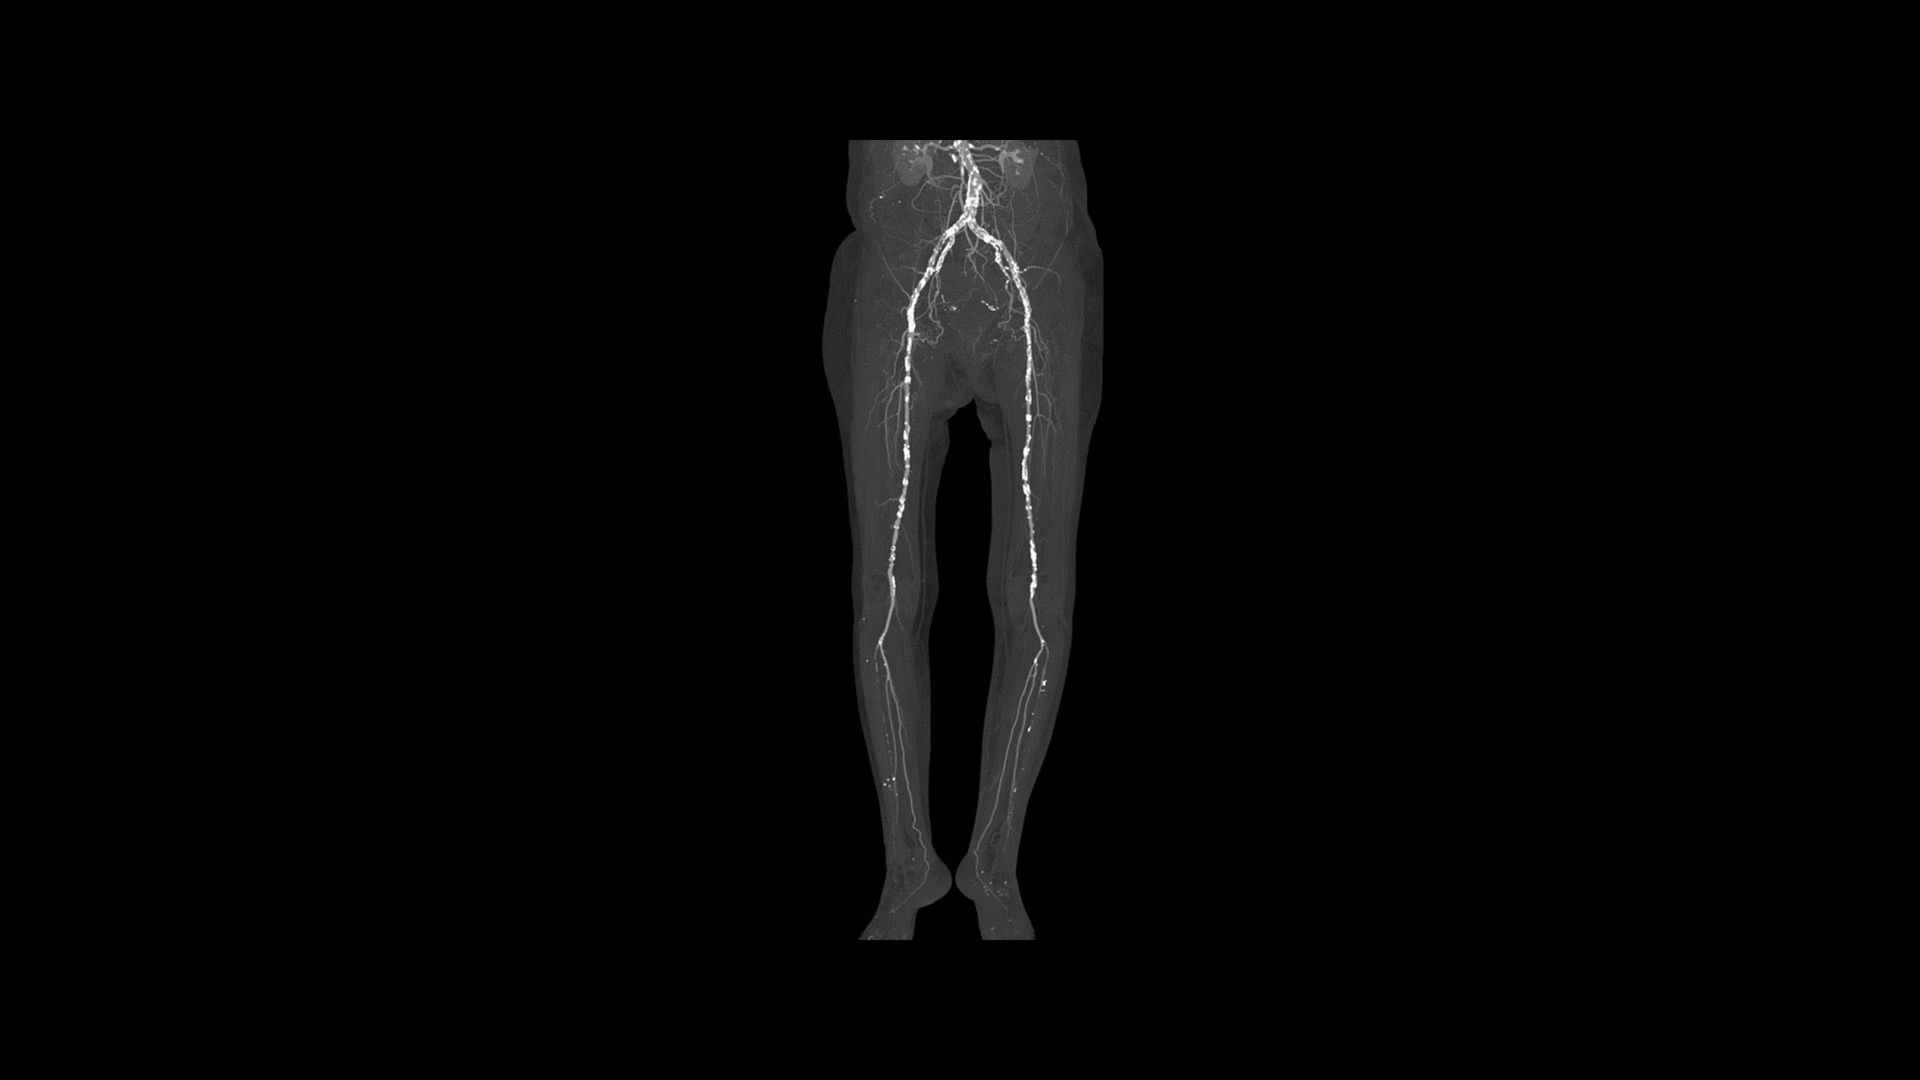

Advanced Visualization

Elevate your CT imaging with our collection of advanced visualization applications that assist reading, automate post-processing and streamline imaging review.